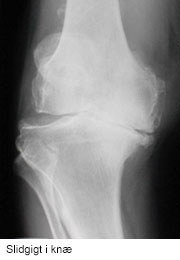

Slidgigt er den mest udbredte ledsygdom, der rammer stort set alle med alderen. Otte ud af ti har slidgigt, når de har passeret de 50 år. Slidgigt opstår, når brusken mellem knoglerne eftrhånden nedbrydes, og det er den mest almindelige årsag til, at der er behov for at indsætte en knæprotese.

De første symptomer er typisk smerter ved igangsætning, ømhed efter belastning og hævelse. Ved svær slidgigt opstår der ofte hvilesmerter, nedsat bevægelighed og måske fejlstilling i ledde.